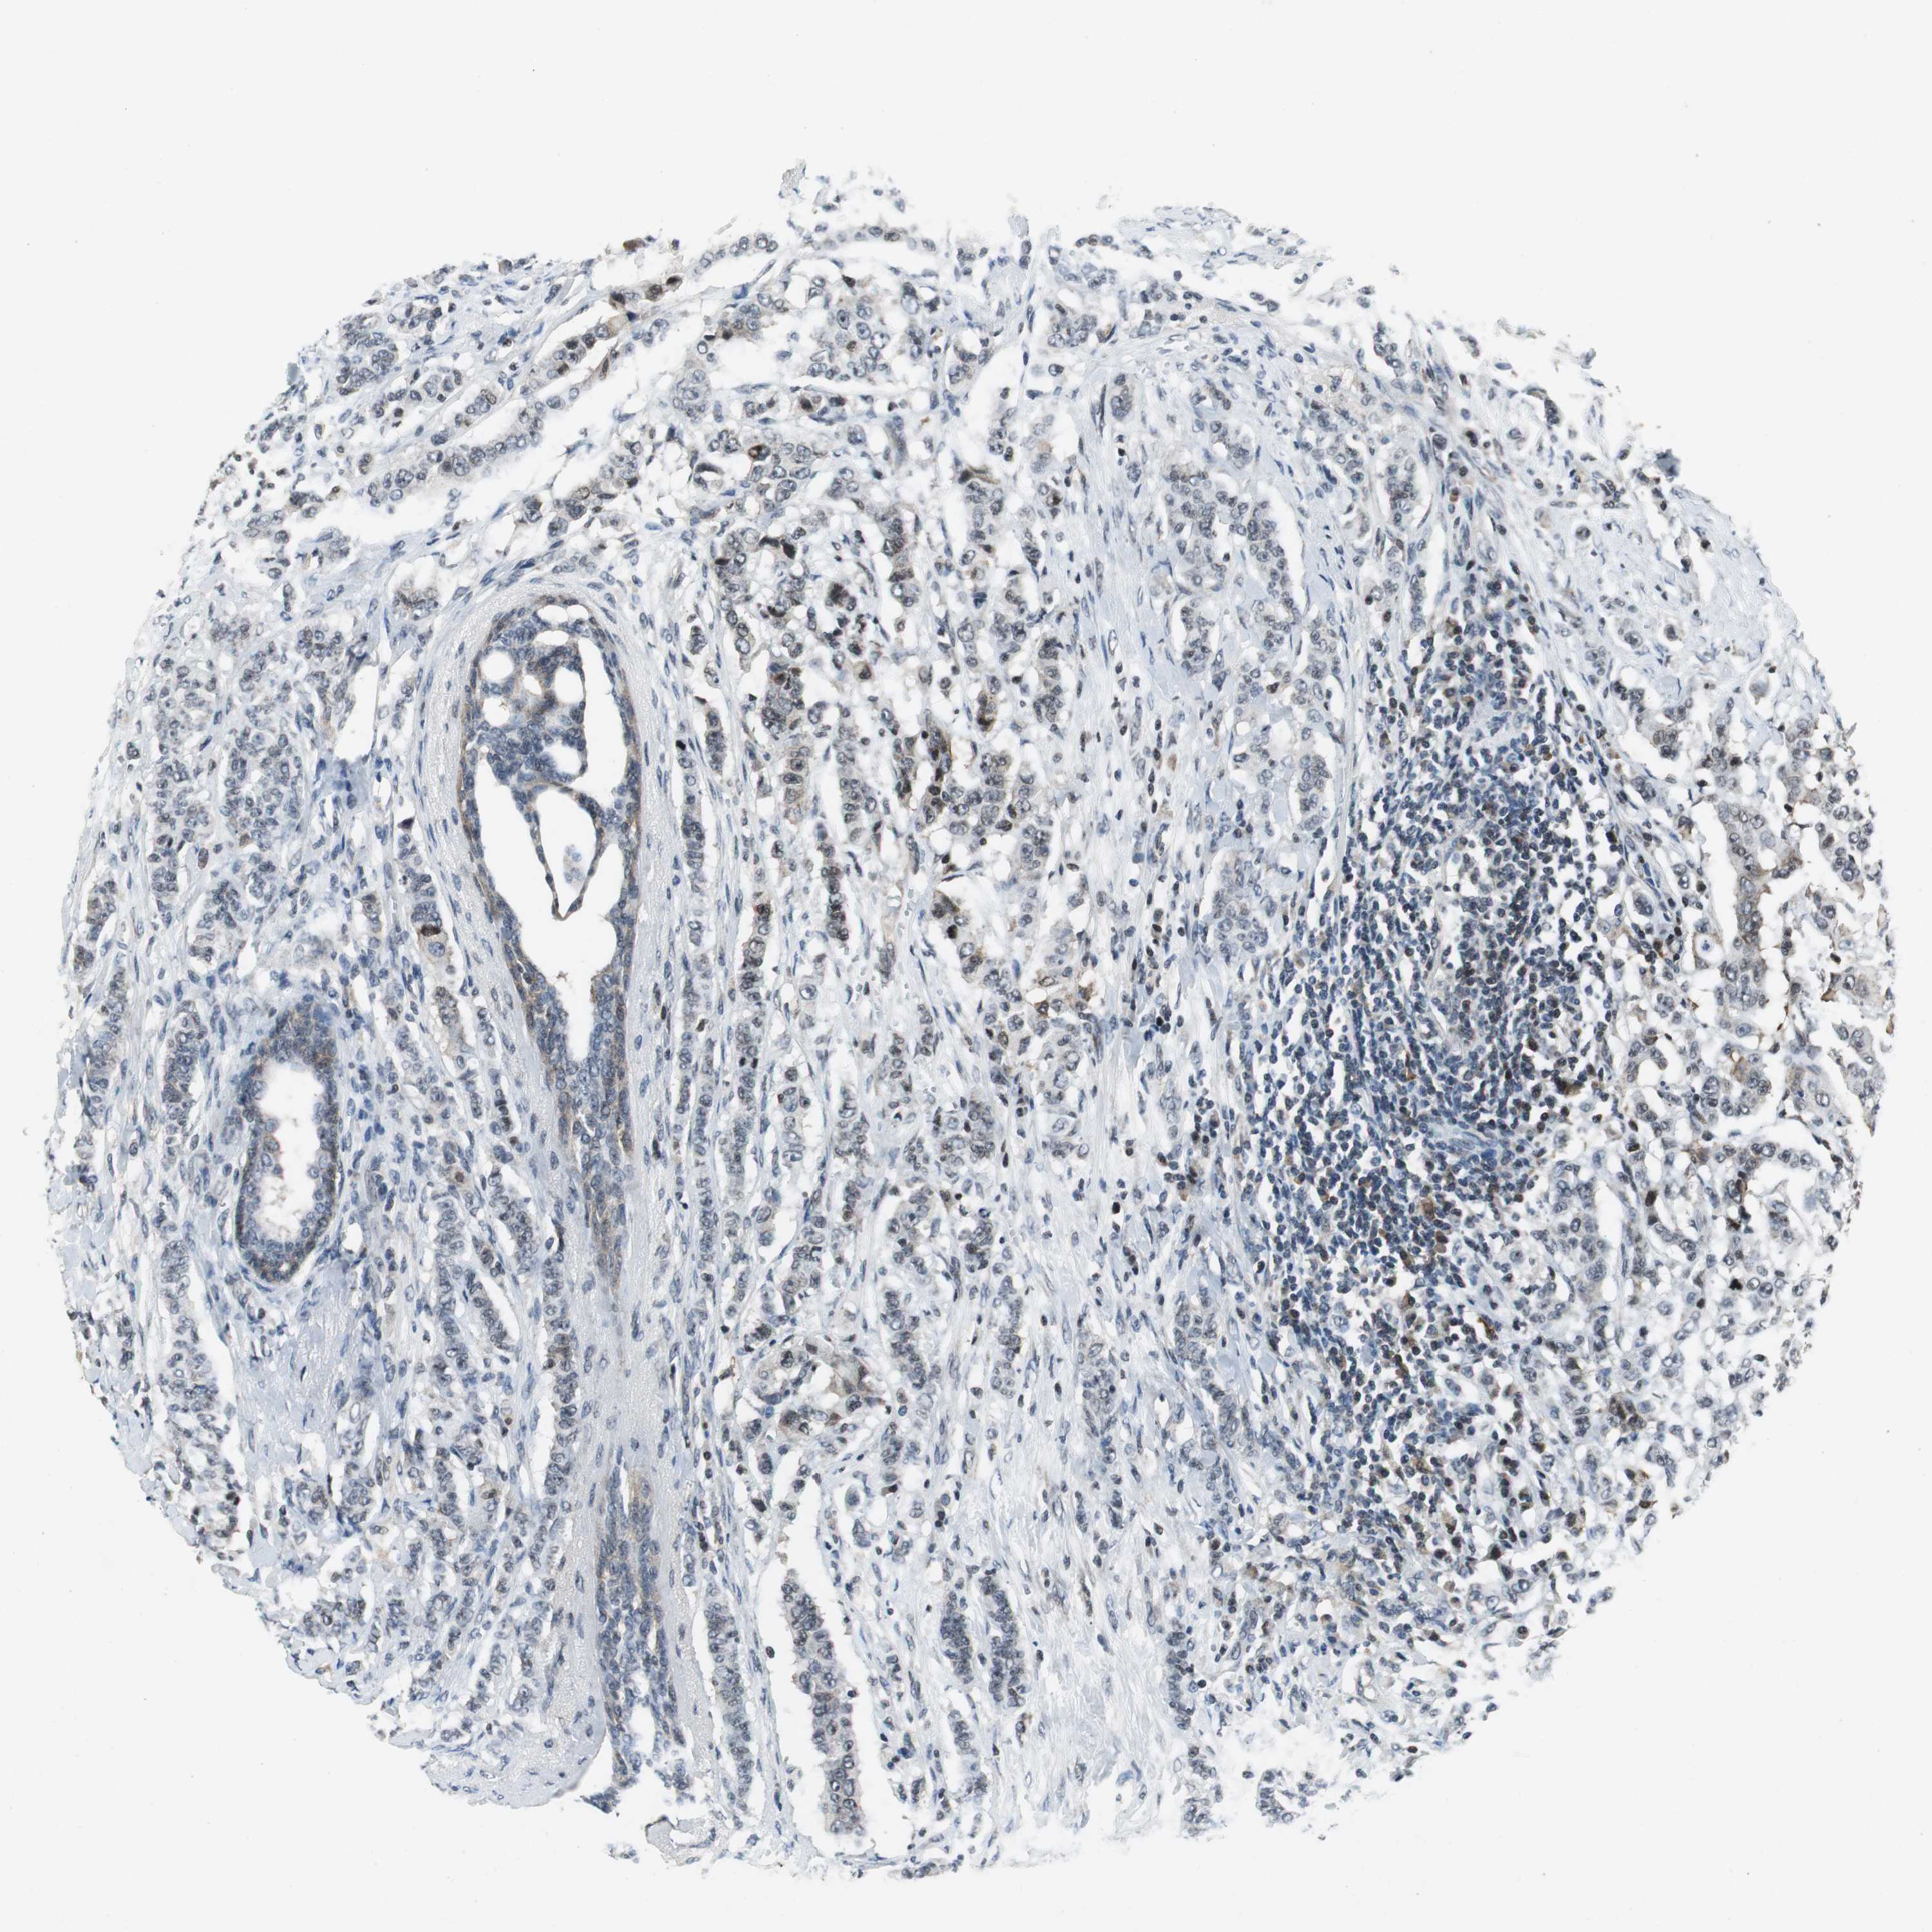

BRCA TCGA BRCA VALIDATION PROTEIN EXPRESSION

ANTIBODIES

AND

VALIDATION